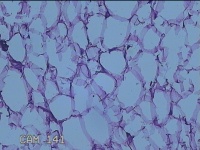

外阴部包块

性别

女

年龄

37岁

临床诊断

皮脂腺囊肿

一般病史

外阴部起包块一月余。

标本名称

大体所见

灰白暗红色包块2.3x1.8x0.8cm一个,表面糜烂,切开包块呈实性,切面灰白淡黄色,质软。

有那么点像脂肪瘤。